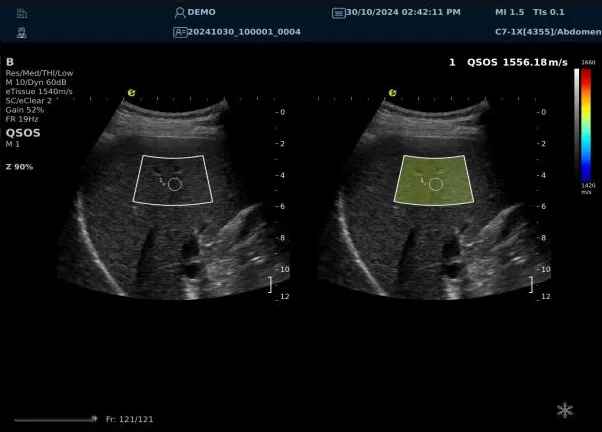

640.jpg123 (2).jpg可以设想,单位时间可发射的脉冲波越多、单位面积可发射的脉冲波越密集,得到的数据结果就越快、越多。也就是说,如果医生希望得到实时、大幅的声速定量图像,就需要超声系统具备“超快速”发射和接收的能力,3377体育医疗(ESI)ePascal东风系列超声平台的200+倍成像速度,成为了这项新技术得以临床应用的重要条件。

以上为应用声速定量成像技术检查肝脏的超声图像,图中在取样框内选择了三个测量区域,得出了各区域内的组织声速值以及声速衰减系数等结果。